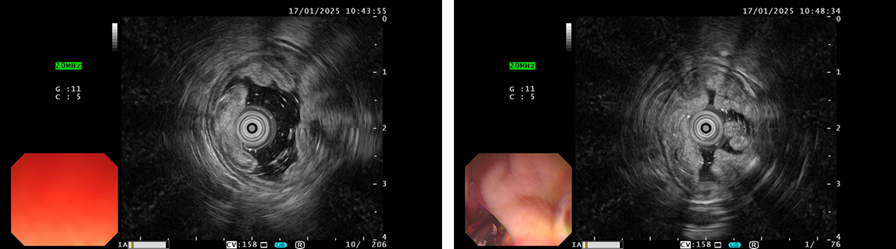

超声胃镜所见:十二指肠降段病变处黏膜层增厚,呈中高回声,黏膜下层及固有肌层完整。考虑十二指肠降段LST。

image.png

图2 超声胃镜检查结果